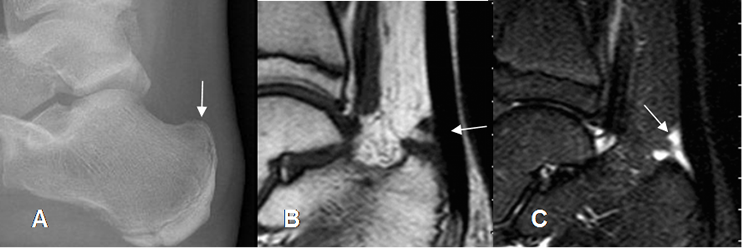

Fig 103. Pinzamiento posterior por sindrome de haglund.

A: Rx lateral. Prominencia del tubérculo del calcáneo, en la parte posterior.

B: RM sagital en T1. Engrosamiento del aquiles por tendinosis.

C: RM sagital en STIR. Presencia de líquido pre-aquiliano, por bursitis.